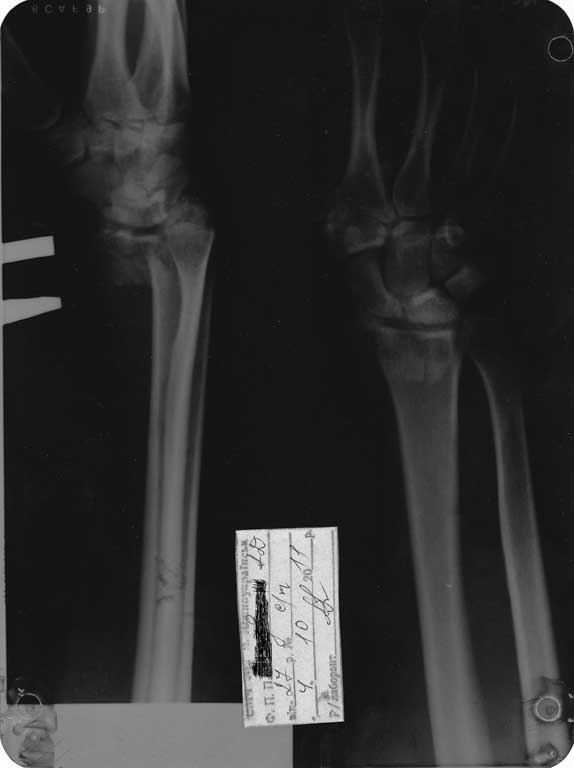

Здравствуйте, уважаемые коллеги!Хочу представить внутрисуставной перелом луча,со

смещением ладонного фрагмента.Имеется подвывих кисти.Закрытая репозиция недостаточна,

после спадения отека тенденция к усилению смещения.Прошу посоветовать оптимальный

У вашего больного нестабильный характер перелома, поэтому консервативное лечение не эффективно. Показана открытая репозиция и фиксация Т образной реконструктивной пластиной по волярной поверхности и чем раньше, тем технически проще будет восстановить анатомию сустава. Важный момент - интраоперационная флюороскопия, позволит избежать неожиданных *сюрпризов* на постоп. Ргграммах и повторных вмешательств.